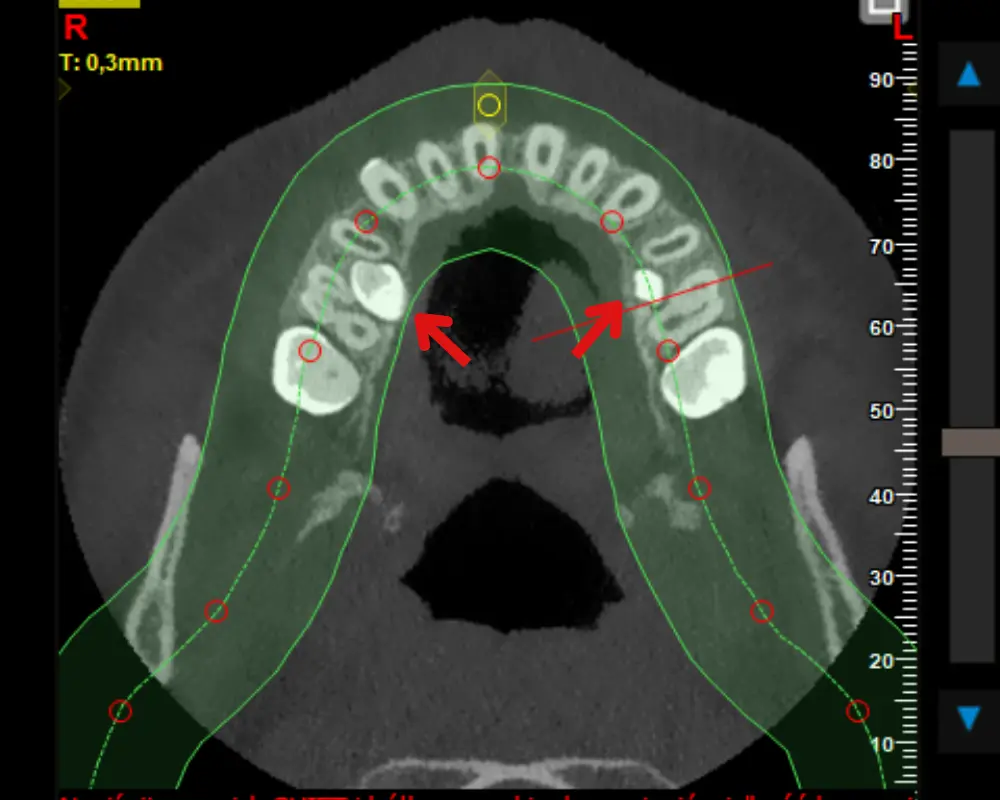

Tomografia CBCT 3D – kiedy standardowe zdjęcia RTG to za mało

W większości przypadków ortodontycznych skaner intraoral, OPG i telerentgen są wystarczające do precyzyjnego zaplanowania leczenia. Jednak niektóre sytuacje kliniczne wymagają głębszego wglądu w struktury kostne i zębowe. Wtedy wykonujemy tomografię komputerową wiązki stożkowej CBCT – badanie dające trójwymiarowy, warstwowy obraz jamy ustnej i twarzoczaszki z dokładnością do ułamków milimetra.

Tomografia CBCT jest szczególnie wartościowa w kilku sytuacjach. Zęby zatrzymane – np. kły górne, które nie wyrżnęły się o czasie – wymagają precyzyjnej oceny ich położenia przestrzennego względem korzeni sąsiednich zębów, aby zaplanować chirurgiczne odsłonięcie i dalsze prowadzenie ortodontyczne. Resorpcje korzeni – czy to samoistne, czy wywołane leczeniem – są znacznie lepiej widoczne na CBCT niż na standardowym RTG. Przy planowaniu implantów po zakończonym leczeniu ortodontycznym CBCT pozwala precyzyjnie ocenić dostępnę kość i zaplanować optymalną pozycję implantu.

W złożonych przypadkach wad szkieletowych II i III klasy, gdzie rozważane jest leczenie chirurgiczno-ortodontyczne, CBCT dostarcza danych niezbędnych do przeprowadzenia wirtualnego planowania operacyjnego (Virtual Surgical Planning). Ortodonta i chirurg szczękowy mogą wspólnie zaplanować ruch szczęki i żuchwy z milimetrową precyzją, zanim pacjent trafi na salę operacyjną.

Zaletą CBCT jest też ocena stawów skroniowo-żuchwowych – głów żuchwy i dołów stawowych – co jest istotne przy współistniejącym bruksizmie lub dysfunkcji SSŻ. Możliwości tomograficzne w naszej klinice opisuje strona tomografia komputerowa 3D, w tym tomografia stawów skroniowo-żuchwowych.

- CBCT 3D – trójwymiarowy obraz kości i zębów z precyzją ułamków milimetra

- Niezbędna przy zębach zatrzymanych i planowaniu ich ortodontycznego prowadzenia

- Ocena resorpcji korzeni w trakcie i po zakończeniu leczenia

- Podstawa planowania chirurgiczno-ortodontycznego (Virtual Surgical Planning)

- Ocena stawów SSŻ przy współistniejącym bruksizmie lub dysfunkcji

- Planowanie implantów po leczeniu ortodontycznym – ocena dostępnej kości